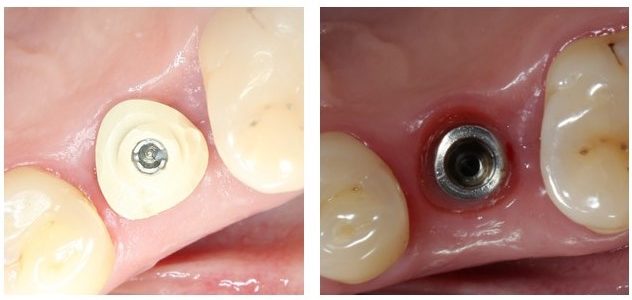

Через три месяца мы сняли коронки с имплантатов, чтобы оценить качество формирования десневого контура:

С этого момента можно перестать переживать — десневой контур сформировался правильно, мы получили достаточный объём и качество окружающей платформу имплантата десны. Можно приступать к изготовлению постоянной протетики. Подрядчиком стала зуботехническая лаборатория French Creative, одна из топовых лабораторий Москвы.

На фотографиях с временными коронками, — я уверен, вы обратили на это внимание, — шахты фиксирующих винтов выходят на режущий край:

Поэтому для постоянных протетических конструкций мы выбрали цементную фиксацию на индивидуальных абатментах.